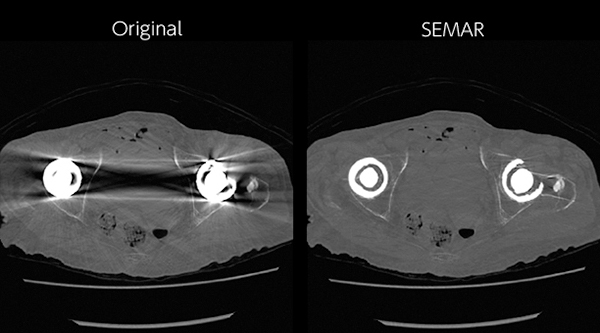

画質に影響を与えるアーチファクトを効果的に低減する各技術を搭載。息止め不良の影響や,撮影中の体動のほか,金属や腕下ろし時のアーチファクトなどの影響を抑制します。患者さんの状態に左右されない,安定した画像をご提供します。

・金属アーチファクト低減技術:SEMAR

※Single Energy Metal Artifact Reduction:SEMAR